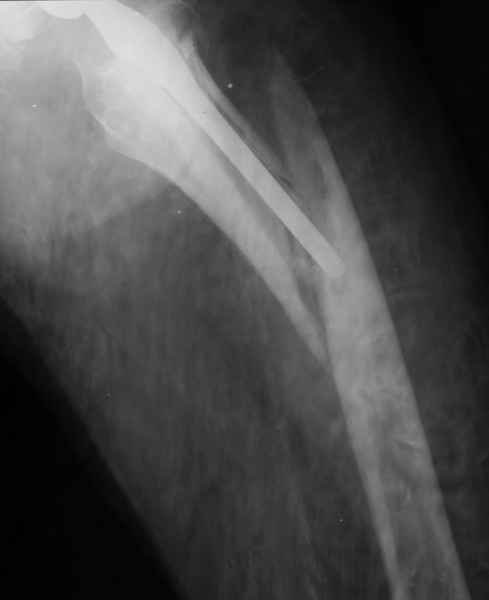

1.Остеосинтез на ножке. Мне кажется, что применительно к этому случаю малоперспективный вариант. Синтез хорош, когда можно его выполнить в малоинвазивном исполнении и достигнуть стабильности. Действительно, если ножка б/цементной фиксации после этого не будет иметь фиксации, то ревизия не будет иметь проблем. В представленном случае стабильность синтеза сомнительная, а проведение доп.иммобилизации приведет к контрактуре суставов.

2. Применение ножки дистальной фиксации, мы отдаем предпочтение ножке Вагнера с фиксацией проксимального отдела на ножке. Более травматичное вмешательство, но при стабильной фиксации ножки реабилитация идет в обычном режиме.

Хочется показать два подобных случая, П-ка З. 72 лет и п-т Г. 80 лет. Сразу принимаю замечание, что это были ножки цементной фиксации, просто под руками не было бесцементника.